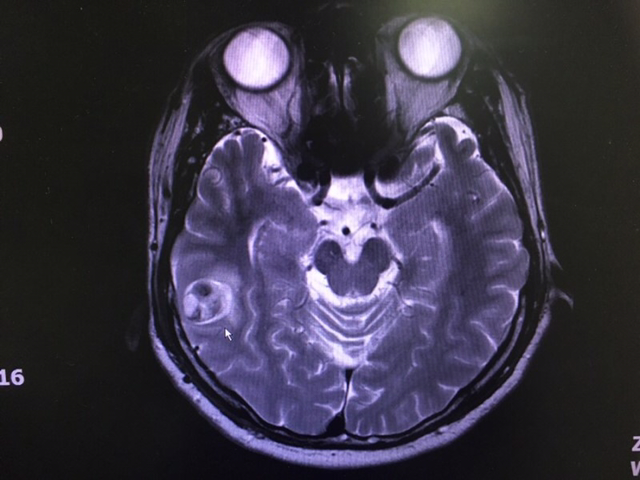

MRI까지 살폈더니 AVM이 포착된다.

뇌동정맥 기형은 선천적 발달 이상으로

동맥이 모세혈관을 거치지 않고 바로

정맥으로 연결되는 혈관의 기형이다.

뇌동정맥 기형(AVM : arteriovenous malformation)